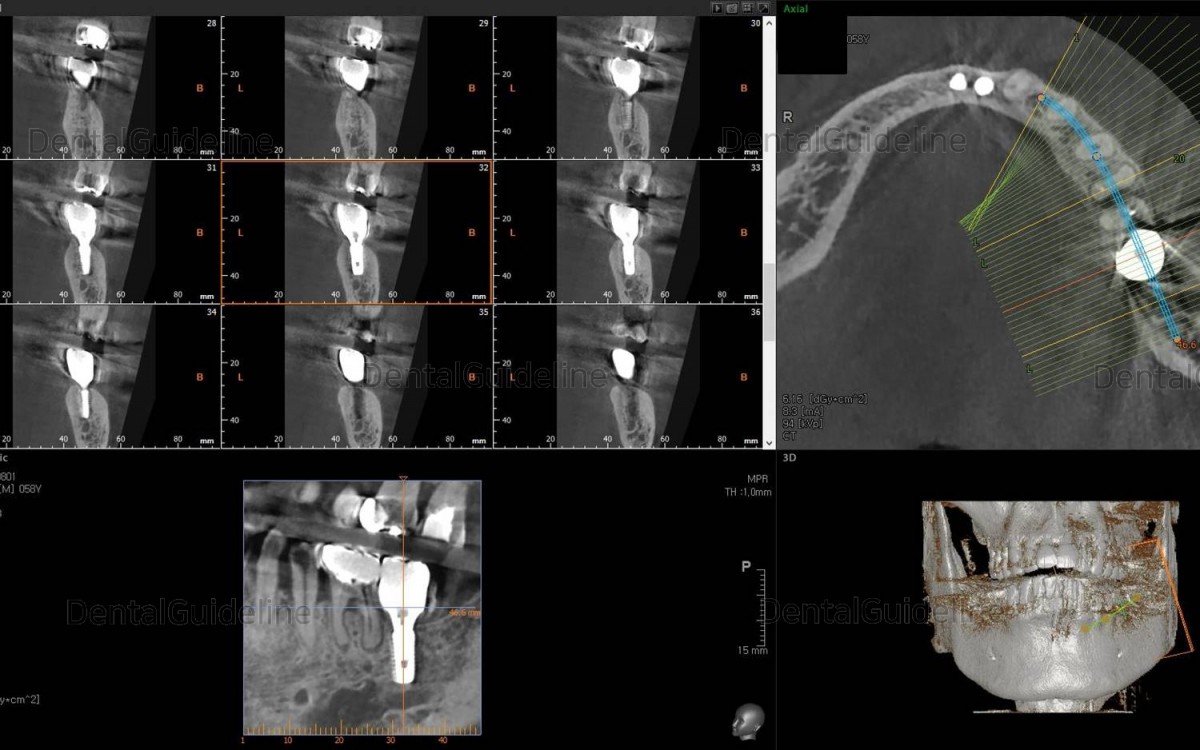

Post-op CBCT.

About 3.5 months after the placement of the implant.

ISQ measurement with Osstell IDX kit